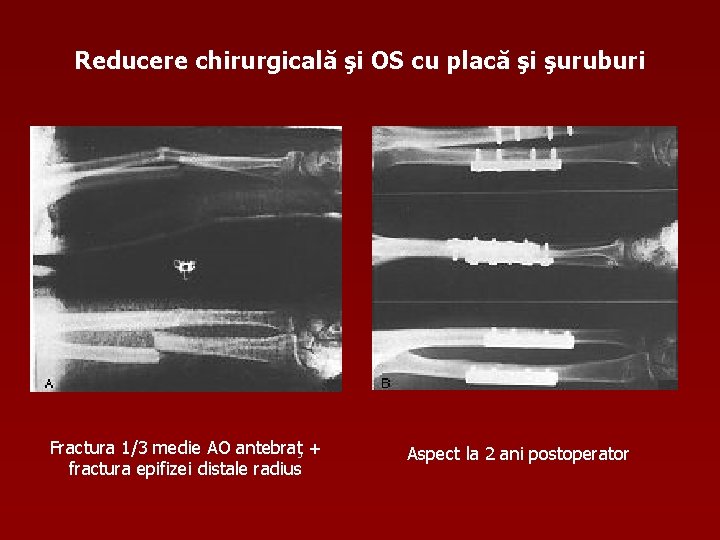

Reducere chirurgicală şi OS cu placă şi şuruburi Fractura 1/3 medie AO antebraţ + fractura epifizei distale radius Aspect la 2 ani postoperator